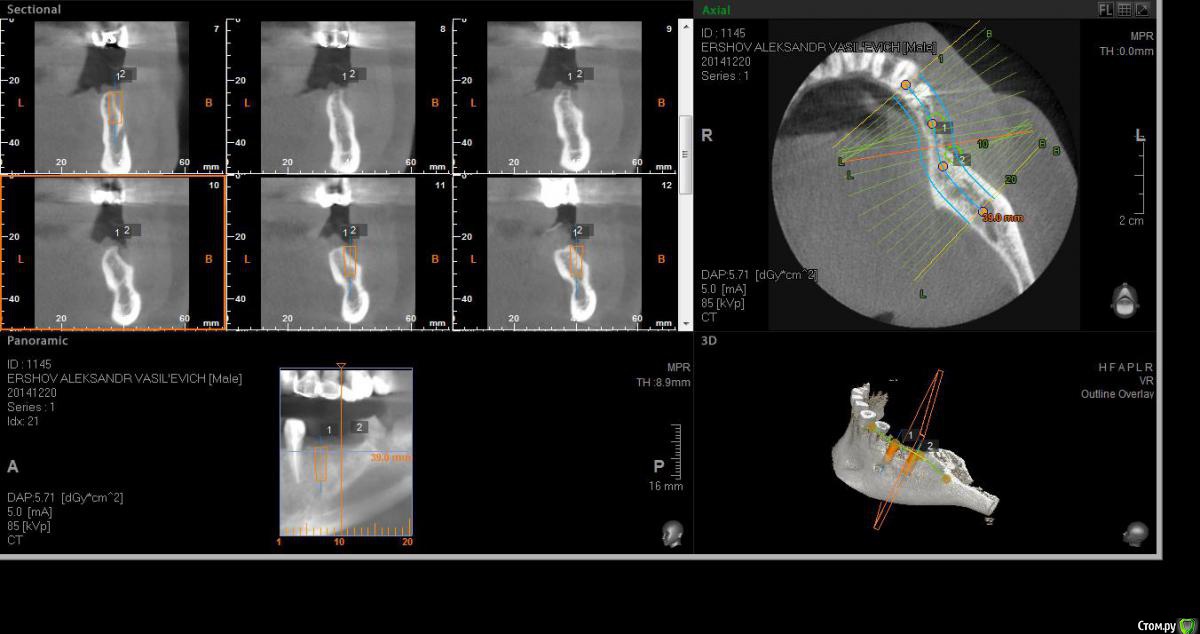

Neilrus Опубликовано 14 января, 2015 Поделиться Опубликовано 14 января, 2015 Здравствуйте. посмотрите мой случай, пожалуйста, и помогите добрым советом. планирую операцию в 3 сегменте импланаты 4,2*10 mis seven по месту 35, 36 зубов, про нехватку костной ткани все понятно, но у меня вопрос к докторам с опытом, можно одномоментно поставить имплантаты как на фотографиях, учитывая форму гребня + МПК (Curved+MP3+ауто со сверла)...или все же не спешить и сделать сначала остеосинтез МПК, а через полгода поставить имплантаты? Как быть конкретно в этой ситауции, когда щечно имплантат будет оголен на половину длины почти, расщепить форма гребня не позволяет ЗАранее спасибо за советы. 35 зуб: 36 зуб (есть риск провалиться, но, мне кажется, кортикалка толстая язычно, должно быть норм) Ссылка на комментарий

АнтонТЛТ Опубликовано 14 января, 2015 Поделиться Опубликовано 14 января, 2015 36 неправильно спозиционирован относительно антогониста. 35 посмотрите, что вообще от кости останется после подготовки имплантационного ложа. Посмотрите где хотите фиксировать каркас относительно ментального отверстия.Почему seven, а не M4?Длину можно взять покороче, чтоб не проваливаться.Рекомендую пластику и имплантацию разделить по этапам. Ну и десну потом подкинуть 5 Ссылка на комментарий

Alejandro Опубликовано 15 января, 2015 Поделиться Опубликовано 15 января, 2015 На нижней челюсти лучше двухэтапно, или расщепляться. И лучше М4 - у него площадь в 1,5 раза больше. Ссылка на комментарий

Чертков Александр Опубликовано 15 января, 2015 Поделиться Опубликовано 15 января, 2015 36 неправильно спозиционирован относительно антогониста. Я бы даже сказал что оба позиционированы не точно. + 1 за два этапа. Ссылка на комментарий